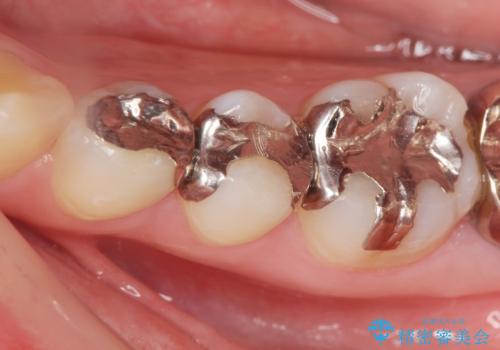

目立つ銀歯を白くしたい

- 銀歯を装着してから時間が経っているので一度外して審美的な修復治療を受けたい、と希望され来院されました。

銀歯周囲の天然歯を削らないよう、拡大鏡下で丁寧に銀歯を除去したのちに審美性・精密性に優れるセラミックインレーを用いた修復治療を行っていきます。